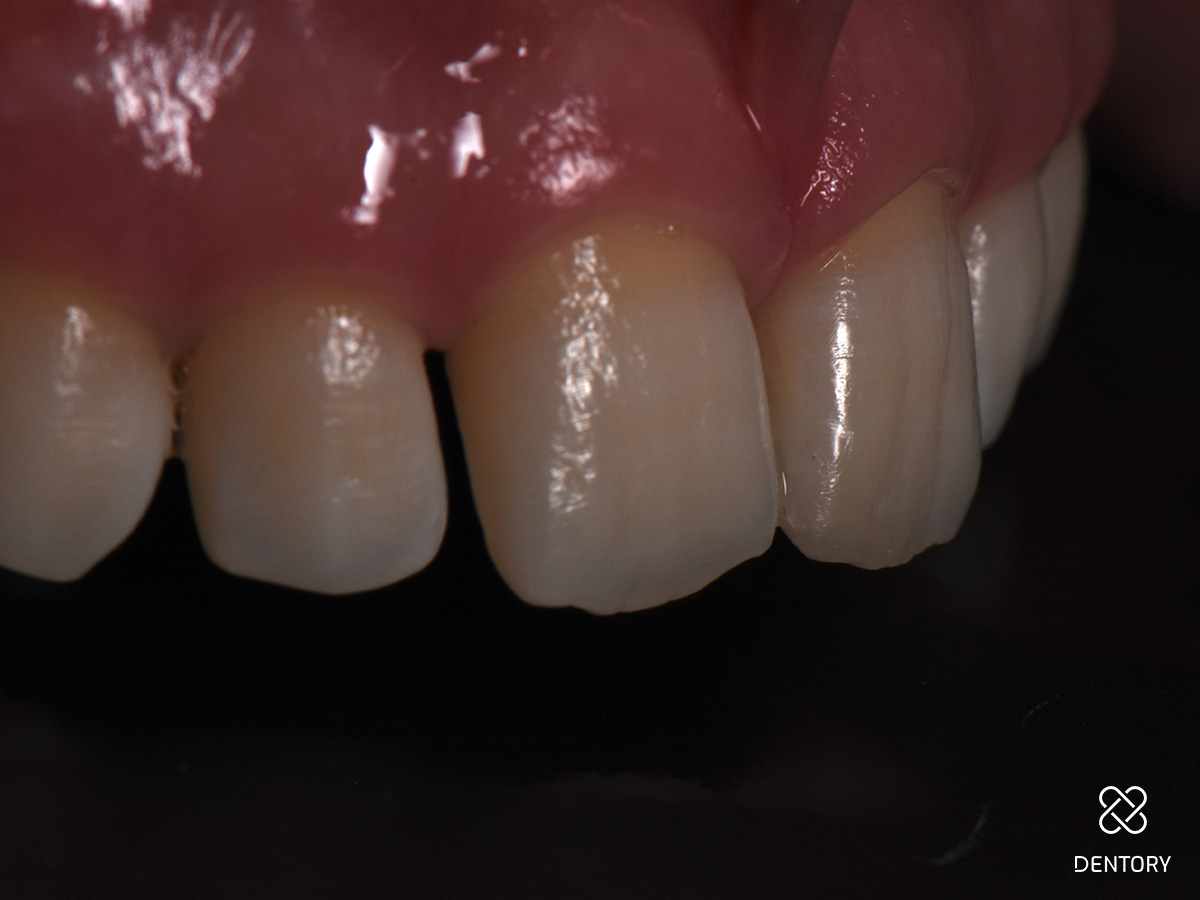

Abbildung 3

Eine breite, wellenförmig verlaufende Anschrägung sorgt für einen fließenden Übergang zwischen Zahn und Restauration hinsichtlich Form und Farbe. Scharfe Kanten und Ecken sollten abgerundet werden.